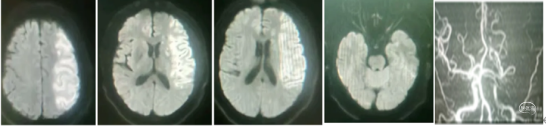

核磁检查显示:左侧额、颞、顶大面积脑梗塞。MRA显示:左侧颈内动脉C5~C6以远未显影。考虑T型段闭塞可能。

影像评估:核磁显示左侧额颞顶部大面积梗塞,但密度不是很高亮,脑沟脑回可见。

CT显示:左侧大脑中动脉上下干区域浅淡低密度改变,CT低密度区域区域大于核磁DWI显示面积。具有挽救的脑组织。